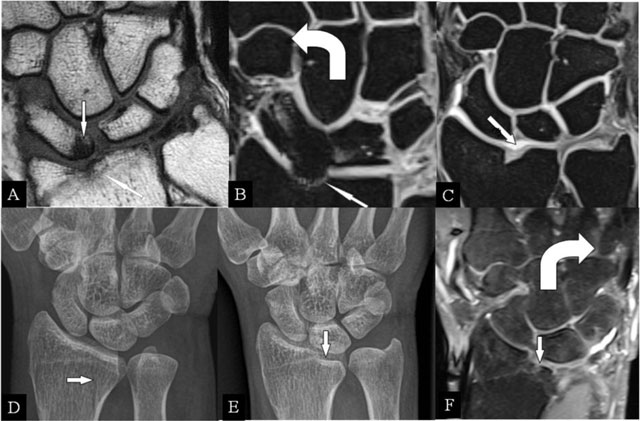

Figure 1

Radioscafoid and radiolunate abutment. (A) Coronal SE T1-WI; (B, C) Coronal 3D-GRE; (D, E) PA plain radiographs; and (F) Coronal SE PD-WI FS. (A) Sequela of an intra-articular fracture of the distal radial epiphysis with a residual step-off (oblique arrow) and marrow oedema (vertical arrow) at the proximal pole of the scaphoid bone. (B) Centrally, the cartilage is destroyed and the radial deviation is blocked. (C) Cartilage step-off in another patient. (D) The parasagittal intra-articular fracture was initially missed. (E) Consolidation with a depressed part of the articular surface. (F) Radiolunate abutment with blocked ulnar deviation.

Radioscafoid abutment

Intra-articular fractures of the radius may heal with a residual step-off [6], seen on radiographs, CT, and MRI (Figure 1A–C). The radial deviation is limited. MRI illustrates the disappeared cartilage (Figure 1A and B) or the surface disruption (Figure 1C). In radial deviation (Figure 1B), bumping of the scaphoid against the prominent radial fossa zone causes repetitive impaction, resulting in BMO.

Radiolunate abutment

Lunate bone impaction on its articular fossa may cause SAS. Parasagittal radial fractures (Figure 1D) need careful follow-up by radiographs or CT [6] in order to detect displacements, possibly causing SAS (Figure 1E and F) and limiting the ulnar deviation (Figure 1F).